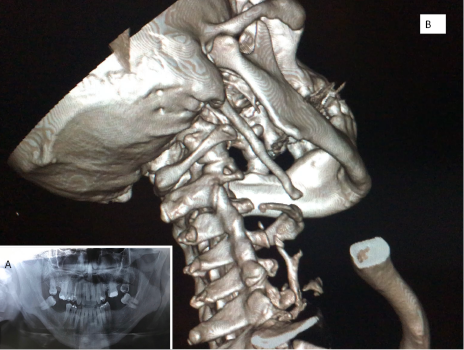

Paciente masculino de 48 años que fue tratado por síndrome de articulación temporomandibular por más de 2 años sin respuesta al tratamiento. Consulta al Servicio de Cirugía donde manifiesta intenso dolor a predominio izquierdo. Detalla cervicalgia, odinofagia, disfagia, otalgia y disminución de la apertura bucal. Solicitamos estudios de rutina y radiografía panorámica (foto 1/A); y con TAC con reconstrucción 3 D fue posible observar que las apófisis se extendían hasta el hioides con una longitud de más de 8 cm (foto 1/B).

Figura 1. 1A. Imagen de radiografía panorámica de maxilares con apófisis estiloides bilateral. 1B. Scan 3D tomográfico con la apófisis que llega al hioides. Fuente: autores.